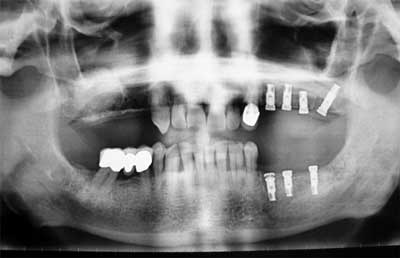

Implantes dentales, inclusiones dentarias (caninos incluidos y cordales o muelas del juicio), quistes y tumoraciones de los maxilares, boca, cabeza y cuello, cirugía de los tejidos blandos de la boca (làser de CO2), patología y cirugía de las encías (periodoncia), cáncer de la boca, deformidades dentofaciales, traumatismos de la boca y de la cara, patología de las glándulas salivares.